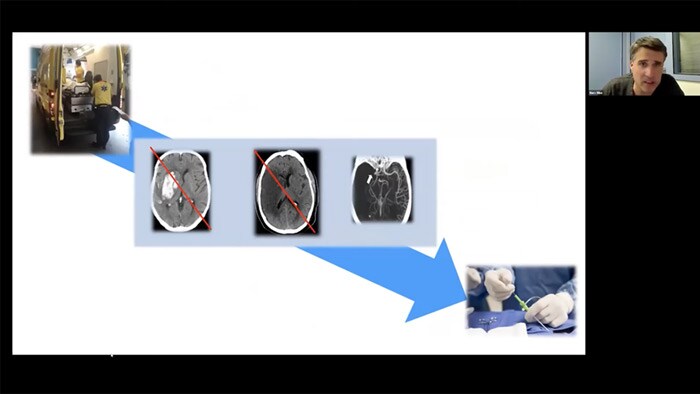

Direct to Angio Suite

Time to reperfusion is fundamental in reducing morbidity and mortality in acute stroke cases1, 2, 3. In patients presenting directly to an endovascular-capable center, emphasis has now been placed on fast door-to-imaging times and fast imaging to groin access times. Watch the video to see how this works.

Experts explain how Direct to Angio Suite workflows shorten door to re-perfusion times for their ischemic stroke patients and how more patients can benefit from mechanical thrombectomy through changed guidelines.